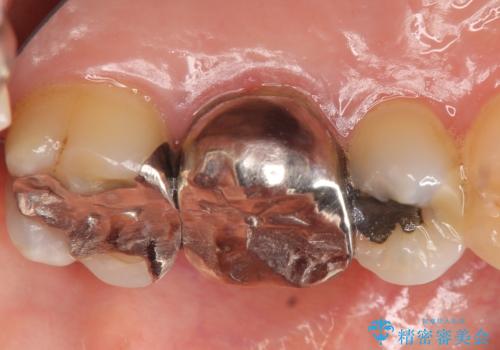

- 左上の奥歯にできものが出来てから口臭が気になるようになったので診て欲しいといらっしゃった方の症例です。

左上のできものは左上6の根尖病変が原因のフィステル(膿の出口)であったため、再根管治療を行いました。